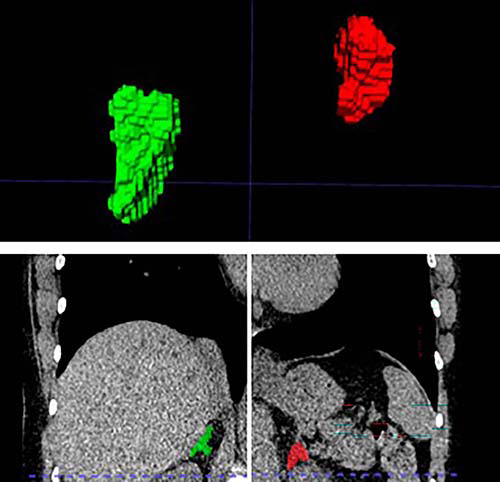

Figure 1. Left and right adrenal automated 2D and 3D segmentation in chest CT.

Figure 2. Left and right adrenal automated 3D segmentation in chest CT.